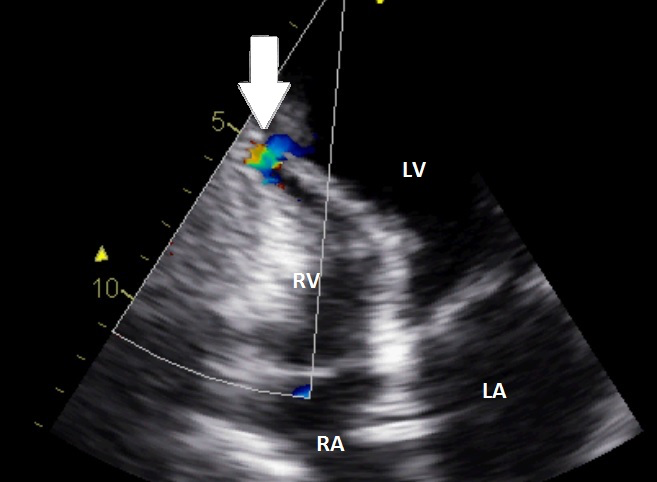

Video 3 / Figuur 3

Let op het blauwe kleursignaal.

Het signaal geeft aan dat de flow van de probe afgaat (blauw) en dus een shunt van links naar rechts weergeeft

Video 3 en figuur 3 betreft wel een voorbeeld echocardiografie van een andere patient met een ventrikelseptumruptuur.

Het VSR zit nl op een andere plaats.

Figuur 3: TTE apicale 4-kamer. De witte pijl geeft de shunt aan en de plaats van de ruptuur.